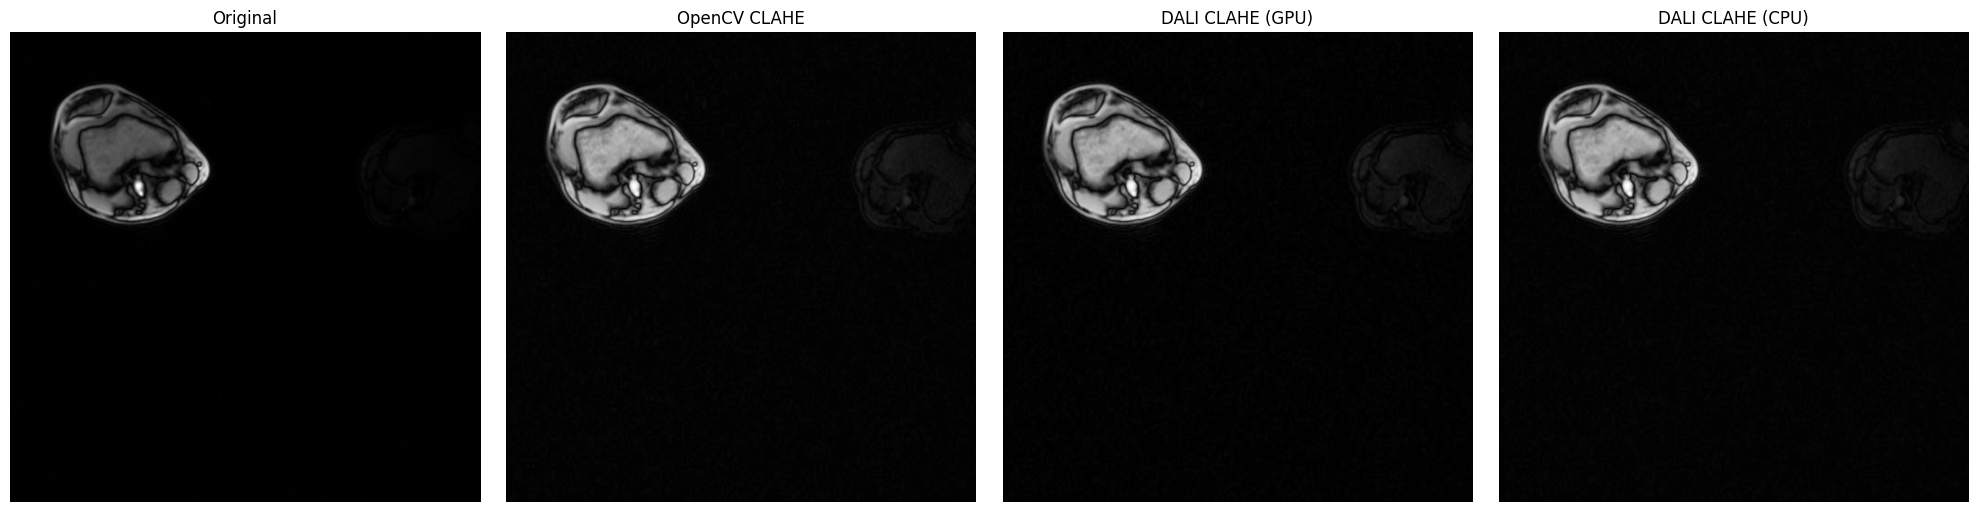

Batch Processing MRI Slices#

Let’s demonstrate a more realistic medical imaging workflow: processing multiple MRI slices in batch. This showcases DALI’s strength in efficient batch processing with GPU acceleration.

Try it yourself: This cell processes multiple MRI slices simultaneously, demonstrating the power of batched CLAHE processing.

[9]:

fig, axes = plt.subplots(2, batch_size, figsize=(5 * batch_size, 10))

plt.suptitle(

print("\nContrast Improvement Analysis:")

Processing 4 MRI slices in batch using NumPy reader...

Contrast Improvement Analysis:

============================================================

Slice 1:

Original std: 19.7, Enhanced std: 33.4

Contrast improvement: 1.70x

Slice 2:

Original std: 20.1, Enhanced std: 33.1

Contrast improvement: 1.65x

Slice 3:

Original std: 18.3, Enhanced std: 31.5

Contrast improvement: 1.73x

Slice 4:

Original std: 17.6, Enhanced std: 29.7

Contrast improvement: 1.69x

Batch processing complete!